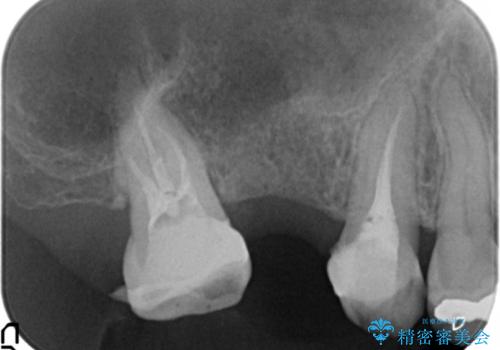

- 上顎臼歯部の欠損にブリッジ治療、目立つ下顎奥歯の銀歯をセラミックへの置き換えを希望され来院されました。

審美性と耐久性に優れるフルジルコニアクラウンでの治療を計画します。